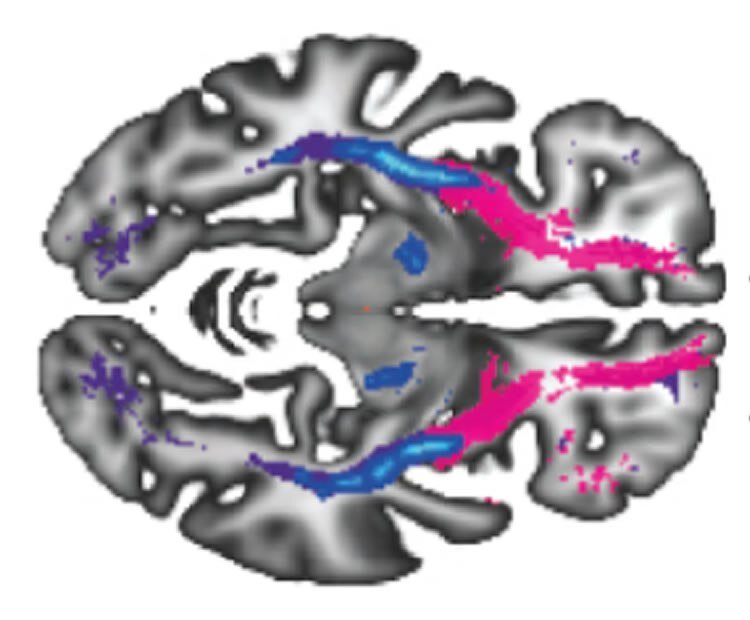

Credit: Alnæs et al

Для анализа томограмм были задействованные специально созданные алгоритмы машинного обучения. Оказалось, что можно найти корреляции между особенностями лобно-височных связей и поперечных волокон крючковидного пучка в ассоциативных волокнах полушарий головного мозга и ранними симптомами психиатрических заболеваний.

«Мы обнаружили, что нарушение волокнистых трактов, соединяющих области мозга, участвующие в эмоциональной регуляции и сложном когнитивном поведении, было связано с более высоким уровнем психических симптомов. Хотя последующие исследования необходимы (а то как же – А.П.), это говорит о том, что аберрантные связи между конкретными областями мозга, присутствующими в молодом возрасте, могут быть связаны с повышенной восприимчивостью к психическим заболеваниям позже в жизни», – говорит ведущий автор работы, Даг Элнес (Dag Alnæs).